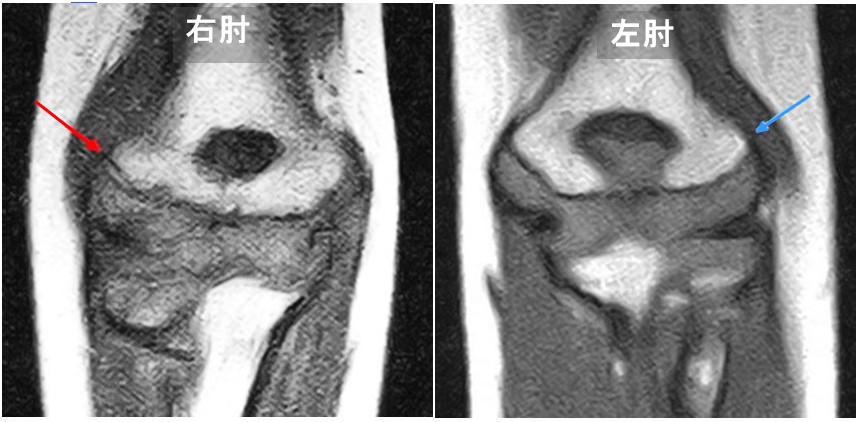

6才男 MR1.jpg

確認のためMR検査を行うと、右肘の赤矢印に骨折を認めました。健側の左肘は骨折線は確認できません。この骨折は上腕骨外顆骨折と呼ばれるもので、見逃されると骨折が治癒せず、あきらかな変形を残したり、大人になっても肘痛や手のしびれの原因となる可能性もある骨折です。ばかにできません。